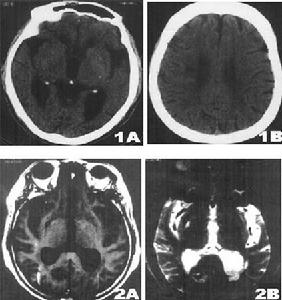

影像學表現:CT表現為斑片狀及斑點狀低密度影,MRI表現為點狀及片狀長T1WI長T2WI信號,由腦深部灰質團塊萎縮,胼胝體繼發變薄,致使腦室擴大,又由於瀰漫性髓鞘脫失而有不同程度的腦萎縮,顯示腦溝增寬,腦池擴大(如圖1~4)。有高血壓及動脈硬化的病理基礎也可發生腦出血是腔隙性梗塞的直接原因。

賓斯旺格病診斷及鑑別診斷:CT,MRI的問世,為本病的生前診斷提供了影像學依據,CT表現為雙側腦室旁白質區與半卵圓中心顯示散在性或融合性低密度區,對稱或大致對稱,基底節,內囊與丘腦區可見多發性腔隙性梗塞,重者伴腦室擴大,其室管膜面多參差不齊,呈碎布狀。MRI表現:在腦室周圍白質與半卵圓中心顯示散在或融合性病變區,T1WI呈黑色,T2WI呈白色。重度與中度顯示腦室擴大,腔隙性梗塞顯影清晰,病灶數目比CT發現的多。SAE應與多發硬化,嚴重腦積水所致的室管膜水腫,CO中毒腦水腫期,腦囊蟲病腦炎型,ALZHEIMER氏病,PICK病,及其他特異性腦白質病,這些腦白質病變根據CT,MRI的表現特點,結合臨床表現60歲以上潛隱起病,逐漸加重,若具備卒中發作,高血壓,慢性進行性痴呆三大臨床特徵,綜合分析,即可做出診斷,也可隨訪複查。

SAE經CT,MRI檢查可明確診斷,CT檢查在發病24h內往往陰性,顯病灶數目少,腦幹,後顱窩病變及視神經通路(視放射)的損害未能顯示而遺漏,但CT價格低,易普及,對腦組織缺氧24h後,CT值即降低,並對缺氧引起的顱內出血及出血量有客觀指標。而MRI在診斷SAE方面比CT更優越,表現在:①MRI在腦細胞毒性水腫6h即可發現病變。②MRI發現病灶數目多。③MRI能夠清楚顯示腦幹,後顱窩病變及視神經通路,顳角部位病變。④MRI可行矢狀,冠狀掃描,多方位觀察。⑤MRI可顯示VIRCHOWROBIN間隙。